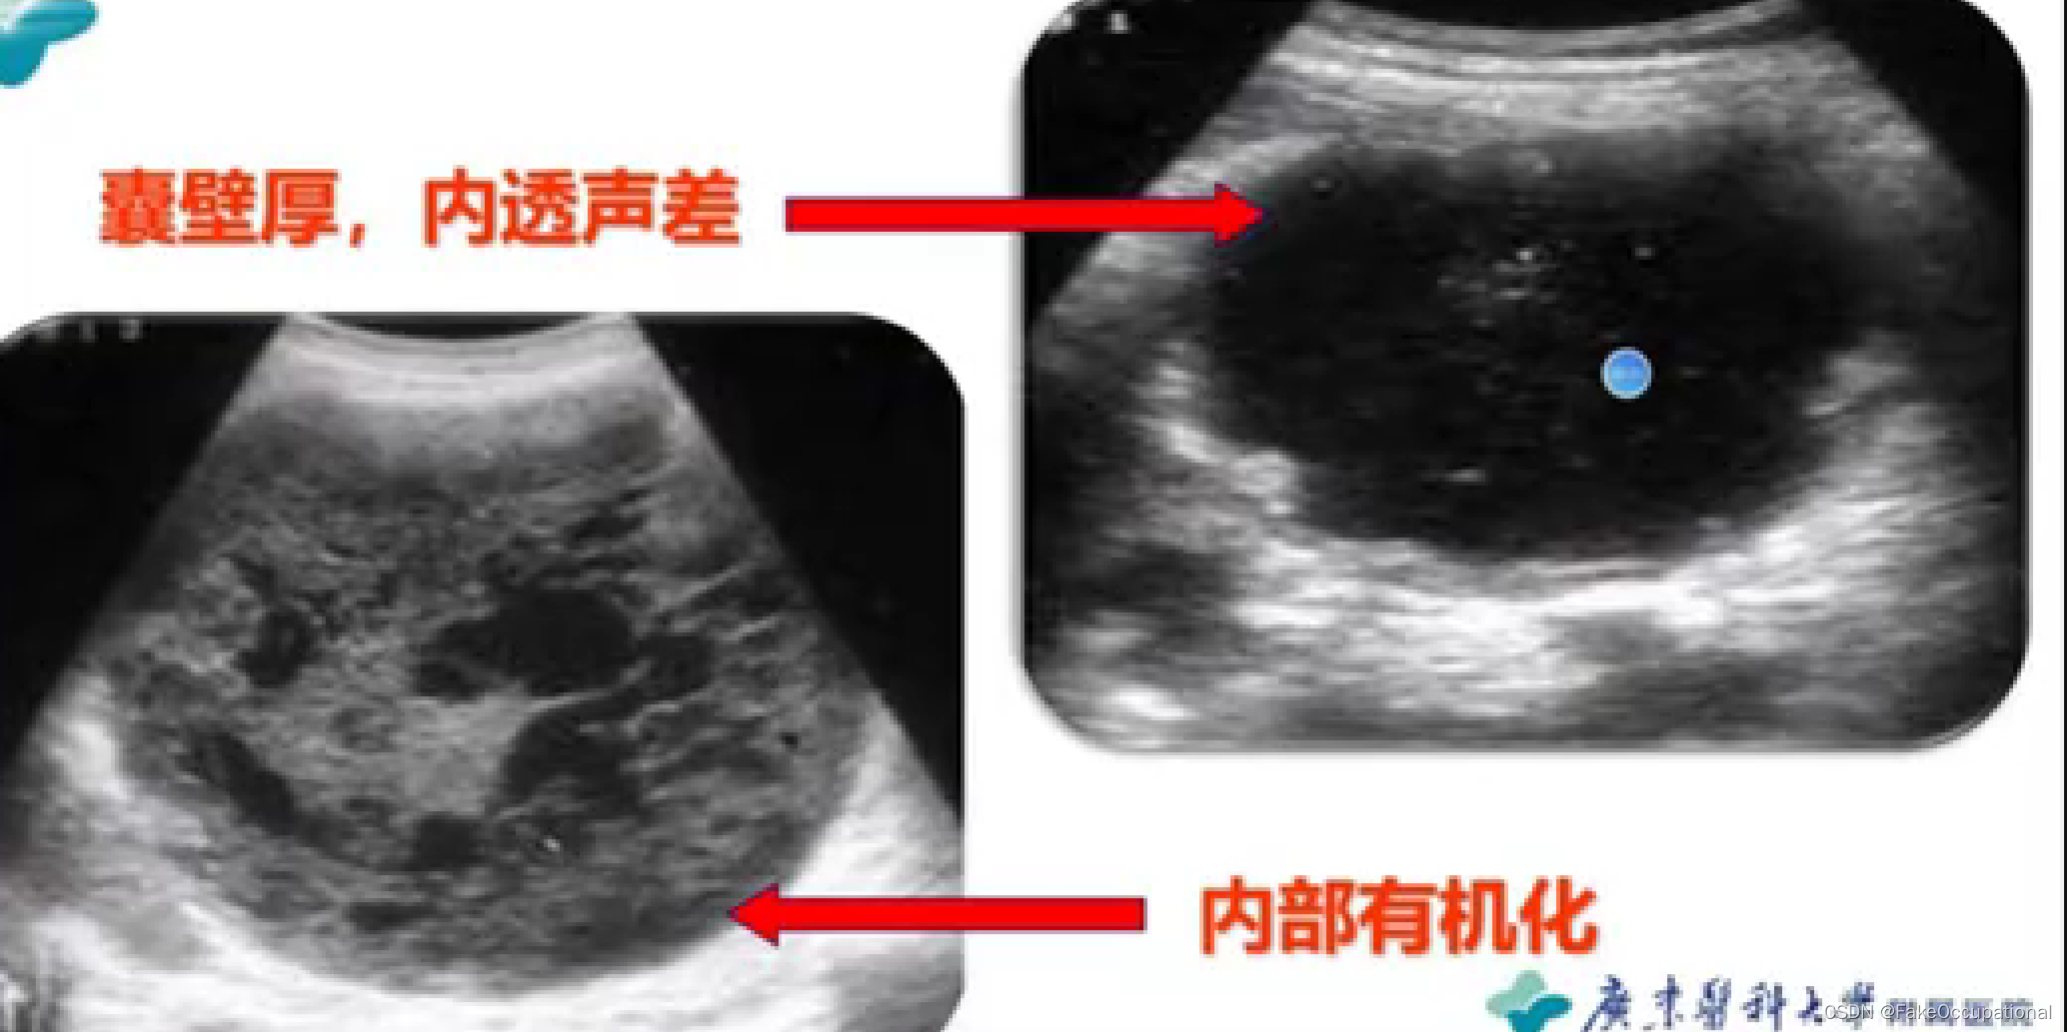

胰腺囊肿—假性囊肿、真性囊肿

胰腺真性囊肿

临床: 胰腺本身形成的囊肿,囊液由囊壁的上皮细胞分泌而来,多数没有临床症状,囊壁比较薄,内透声好.

分类:先天性囊肿

猪留性囊肿

寄生虫性囊肿